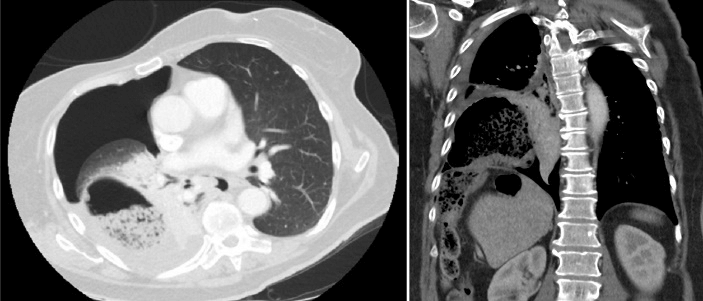

A physical examination at the ED revealed thoracic asymmetry, diminished breathing sounds on the right thorax by auscultation, and no signs of peritonitis. The patient had a tachycardia event, and the oxygen saturation level was 86%. The chest X-ray showed a pneumothorax and atelectasis in the right lobe. An atypical air configuration in the right lower thorax was observed (Figure 1). The patient’s respiratory function and hemodynamics were stable at that point. Therefore, the drainage of the pneumothorax was postponed, and an intravenous contrast-enhanced computed tomography (CT) of the thorax and abdomen was immediately performed, which showed a large pneumothorax with a mild shift of the mediastinum and heart to the left, pleural effusion, atelectasis, and a defect in the right diaphragm with intrathoracic herniation of the ascending colon and a small part of the transverse colon (Figure 2). The terminal ileum was thickened, and signs of inflammation were located in the right upper quadrant.

Figure 2: Axial and coronal computed tomography images before surgery. A right-sided Bochdalek hernia with herniation of the colon is shown.